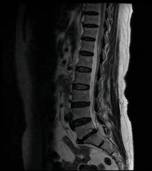

术前MRI检查

患者辗转于西安多家医院,被告知需进行手术治疗,因担心手术较大,出血多,后遗症多,迟迟不能决定手术。经别人推荐慕名找到我院骨科脊柱微创中心的张银刚教授。张银刚教授和刘凯博士等细致了解病情,仔细查体和阅片后分析:该患者腰5-骶1椎间隙退变严重,椎间隙变窄,腰5椎体失稳并向前滑脱,与增生的黄韧带和骨赘组织共同作用,造成腰椎管狭窄。进而引起腰痛、间歇性跛行等症状。

患者,女性,53岁。因患有“腰5椎体滑脱症、腰椎管狭窄症”被腰痛和跛行折磨多年,只能自主行走不到100米。日常生活质量和常规工作受很大影响。病情严重时只能卧床休息,连翻身都很困难。在当地医院查CT和磁共振显示:腰5椎体前滑脱、腰5-骶1节段腰椎管狭窄,黄韧带增厚,关节突关节增生。诊断为“腰5椎体峡部裂,滑脱 、腰椎管狭窄症”。